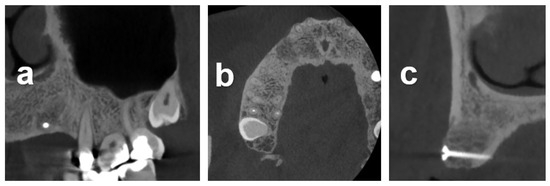

2.7.1. Case 1

2.7.2. Case 2

2.7.3. Case 3

3.2. Radiometric Assessment